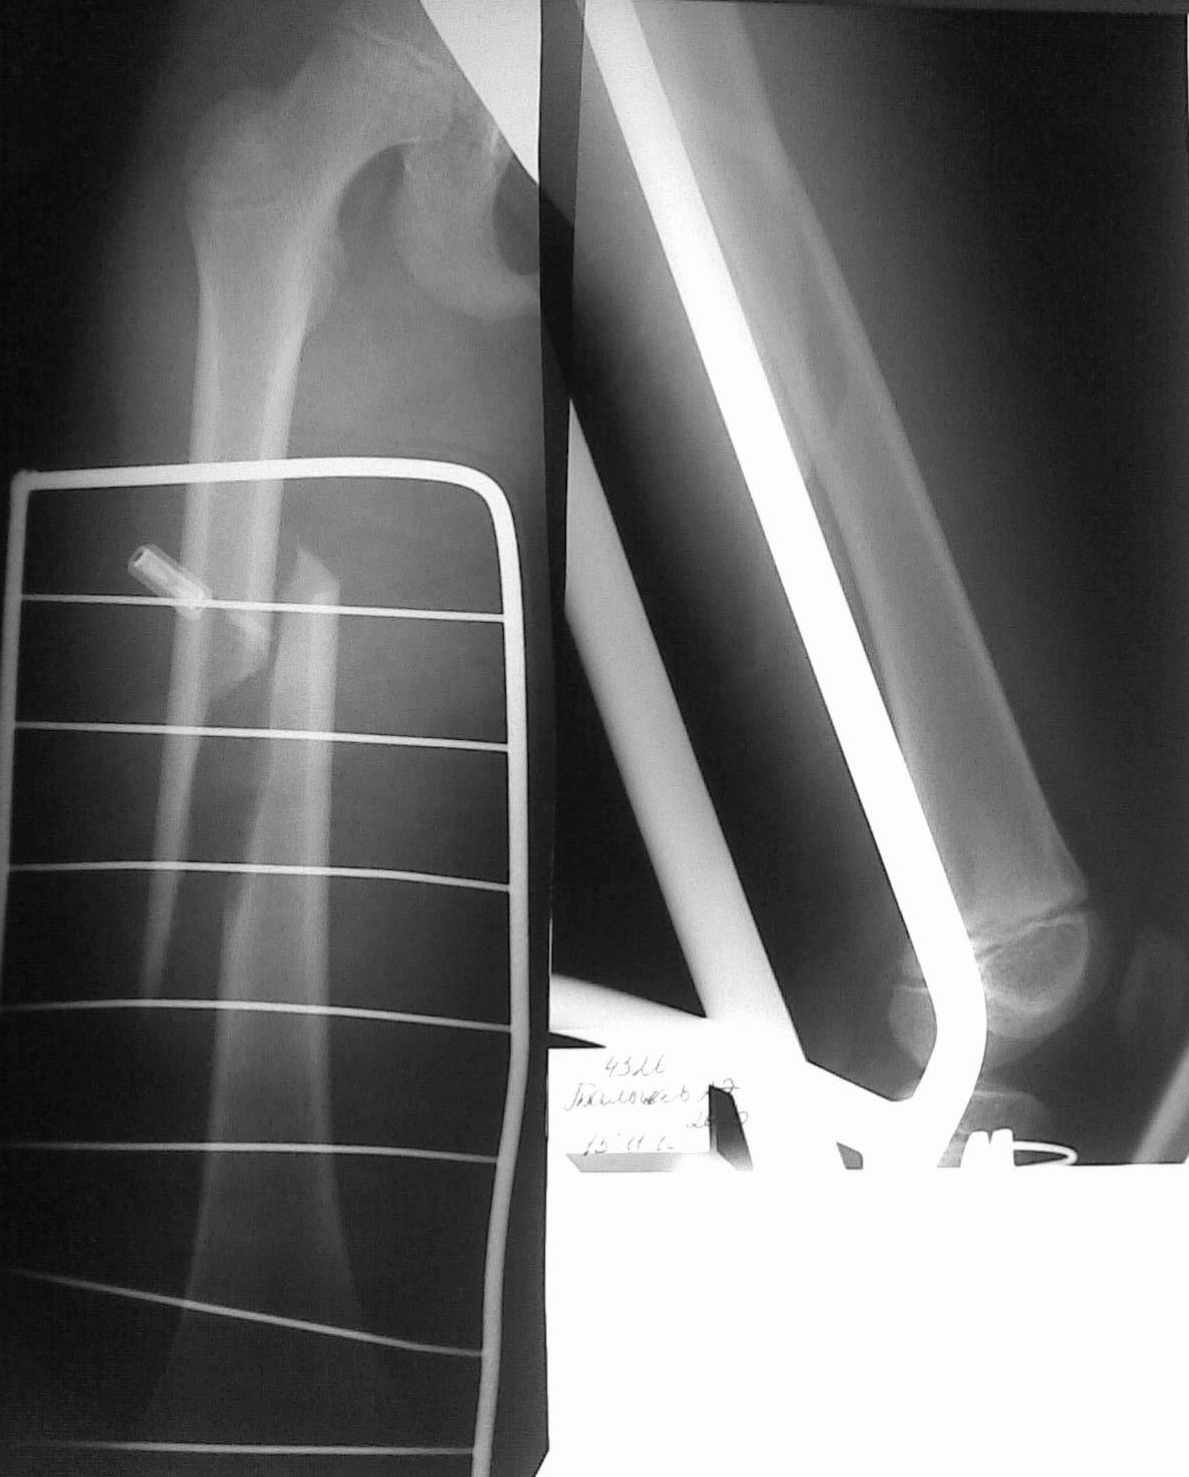

Уважаемые коллеги! В связи с малым опытом лечения переломов трубчатых костей у детей.

хотелось бы узнать Ваше мнение о методах остеосинтеза данного пациента. Ребенок 10 лет,

травма спортивная. есть проблемы с "железом". думаем о интрамедулярном остеосинтезе +

толстый кетгут.